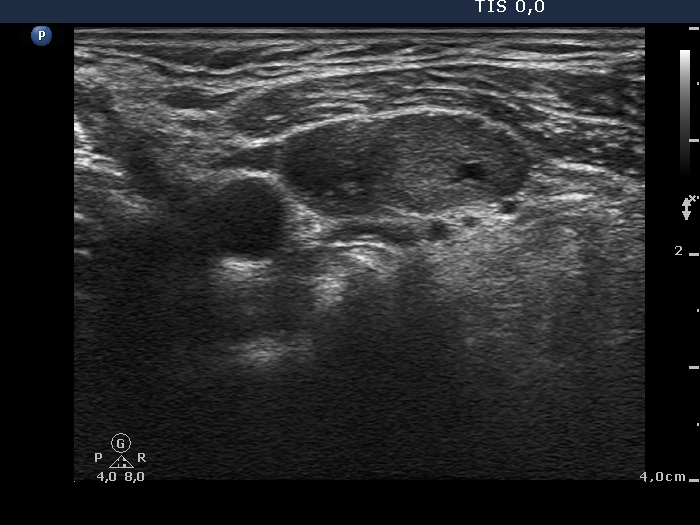

Follow-up examination 17 months after first visit (second and third rows):

Clinical presentation: The patient was well. She came to sonographic follow-up suggested at her first visit.

Palpation: a hard nodule in the upper part of the left thyroid.

Functional state: subclinical hyperthyroidism (TSH undetectable, FT4 21.1 pM/L, FT3 6.68 pM/L).

Ultrasonography: The echogenicity index of the thyroid was 50%. The vascularization was not significantly increased. There was a large hypoechogenic, inhomogeneous nodule in the upper part of the left lobe. Both the intranodular and the perinodular blood flows were increased.